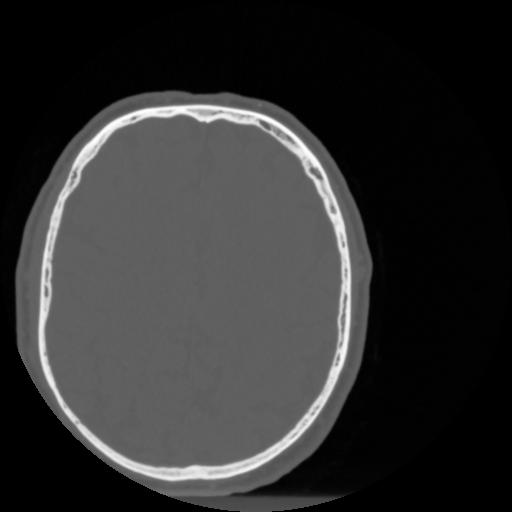

4 CEREBRO,,Vol,0.5,CEREBRO,,